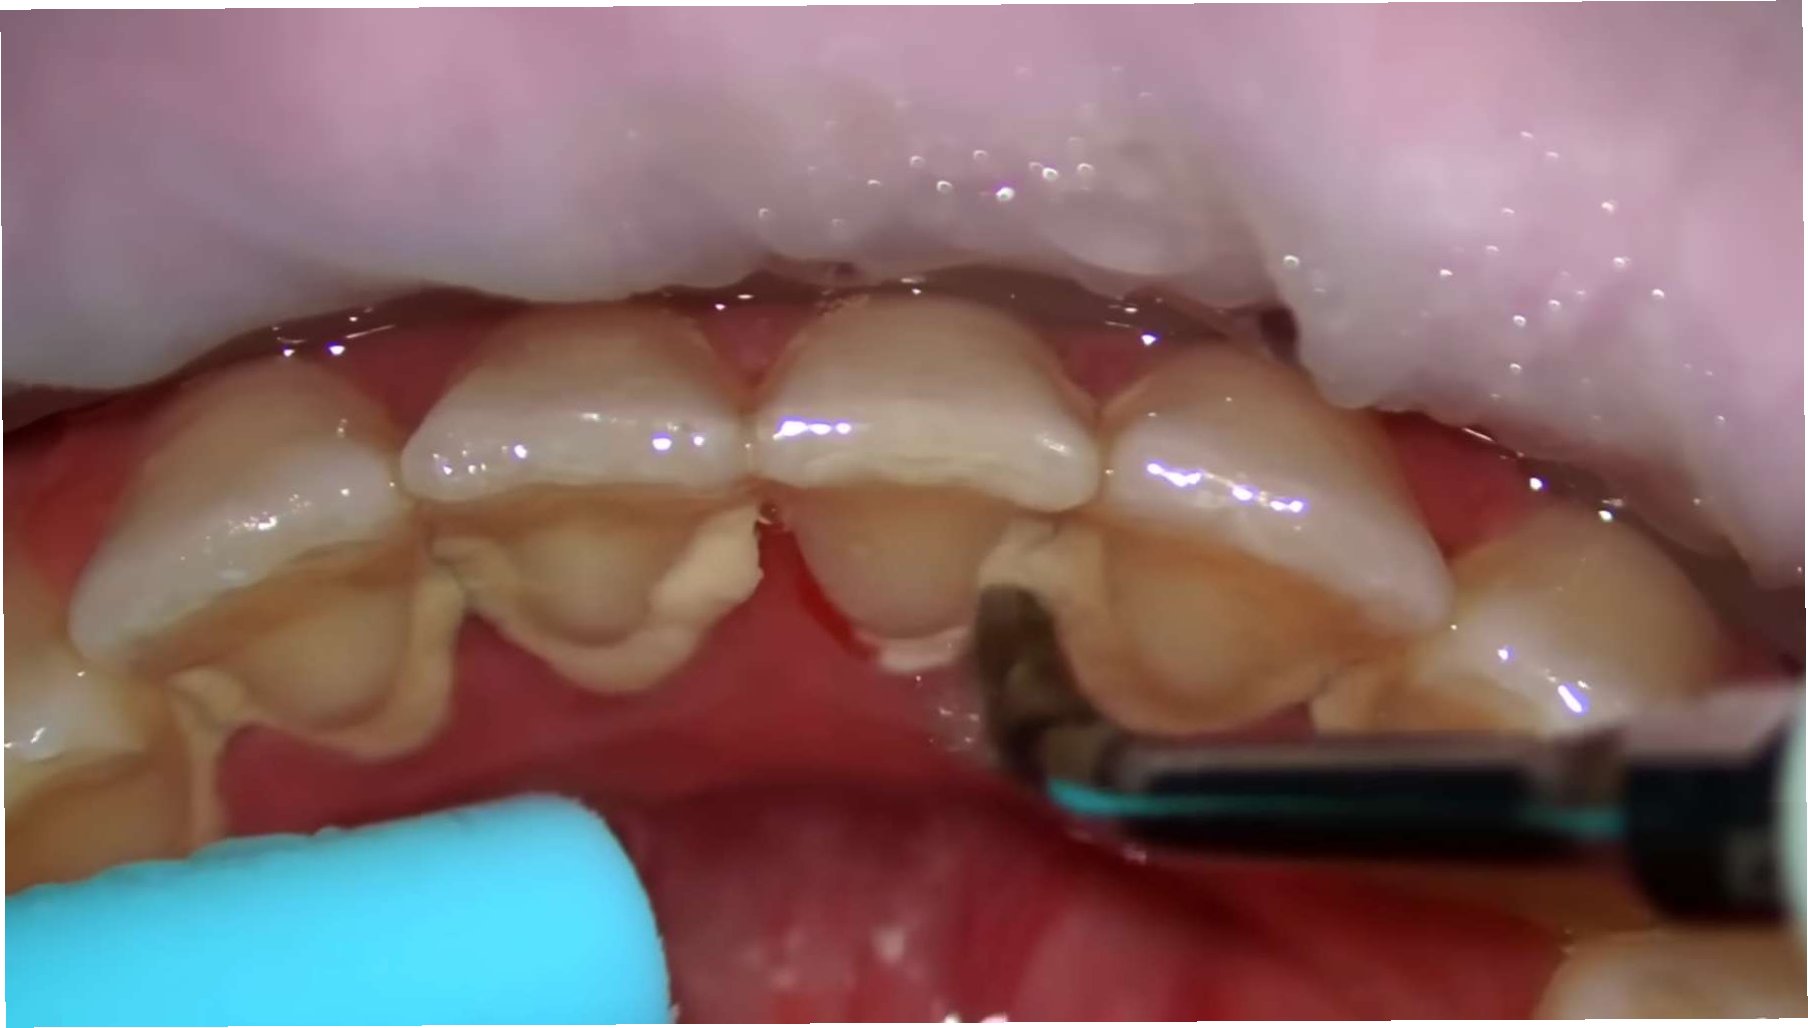

치아 치료는 손상된 치아의 기능을 회복하고, 더 큰 문제로의 확대를 막는 중요한 과정입니다. 충치 치료, 신경 치료, 임플란트, 보철 등 다양한 치료 방법이 있으며, 각 치료는 치아의 상태와 손상 정도에 따라 적절하게 선택됩니다. 그러나 치료받은 치아는 자연 치아보다 관리에 더욱 신경 써야 합니다. 치료 부위는 재발의 위험이 높고, 주변 치아에 영향을 줄 수 있기 때문입니다. 정기적인 치과 검진, 올바른 칫솔질, 치실 사용, 그리고 치아에 무리를 주는 습관을 개선하는 것이 중요합니다. 치료받은 치아를 잘 관리하면, 건강한 치아만큼 오래 사용할 수 있으며, 삶의 질을 유지하는 데 기여합니다.

건강한 치아와 치료받은 치아는 기능, 관리, 그리고 전신 건강에 미치는 영향에서 뚜렷한 차이를 보입니다. 건강한 치아는 자연 상태 그대로의 기능을 수행하며, 특별한 관리가 필요하지 않습니다. 반면, 치료받은 치아는 손상된 부분을 복구한 상태이므로, 지속적인 관리가 필수적입니다. 치료받은 치아는 자연 치아보다 잇몸 질환, 충치 재발 등의 위험이 높으며, 전신 건강에도 영향을 미칠 수 있습니다. 예를 들어, 치주 질환은 심혈관 질환, 당뇨병 등의 위험을 높일 수 있습니다. 따라서, 건강한 치아를 유지하기 위한 예방적인 노력과 치료받은 치아에 대한 꼼꼼한 관리가 중요합니다.